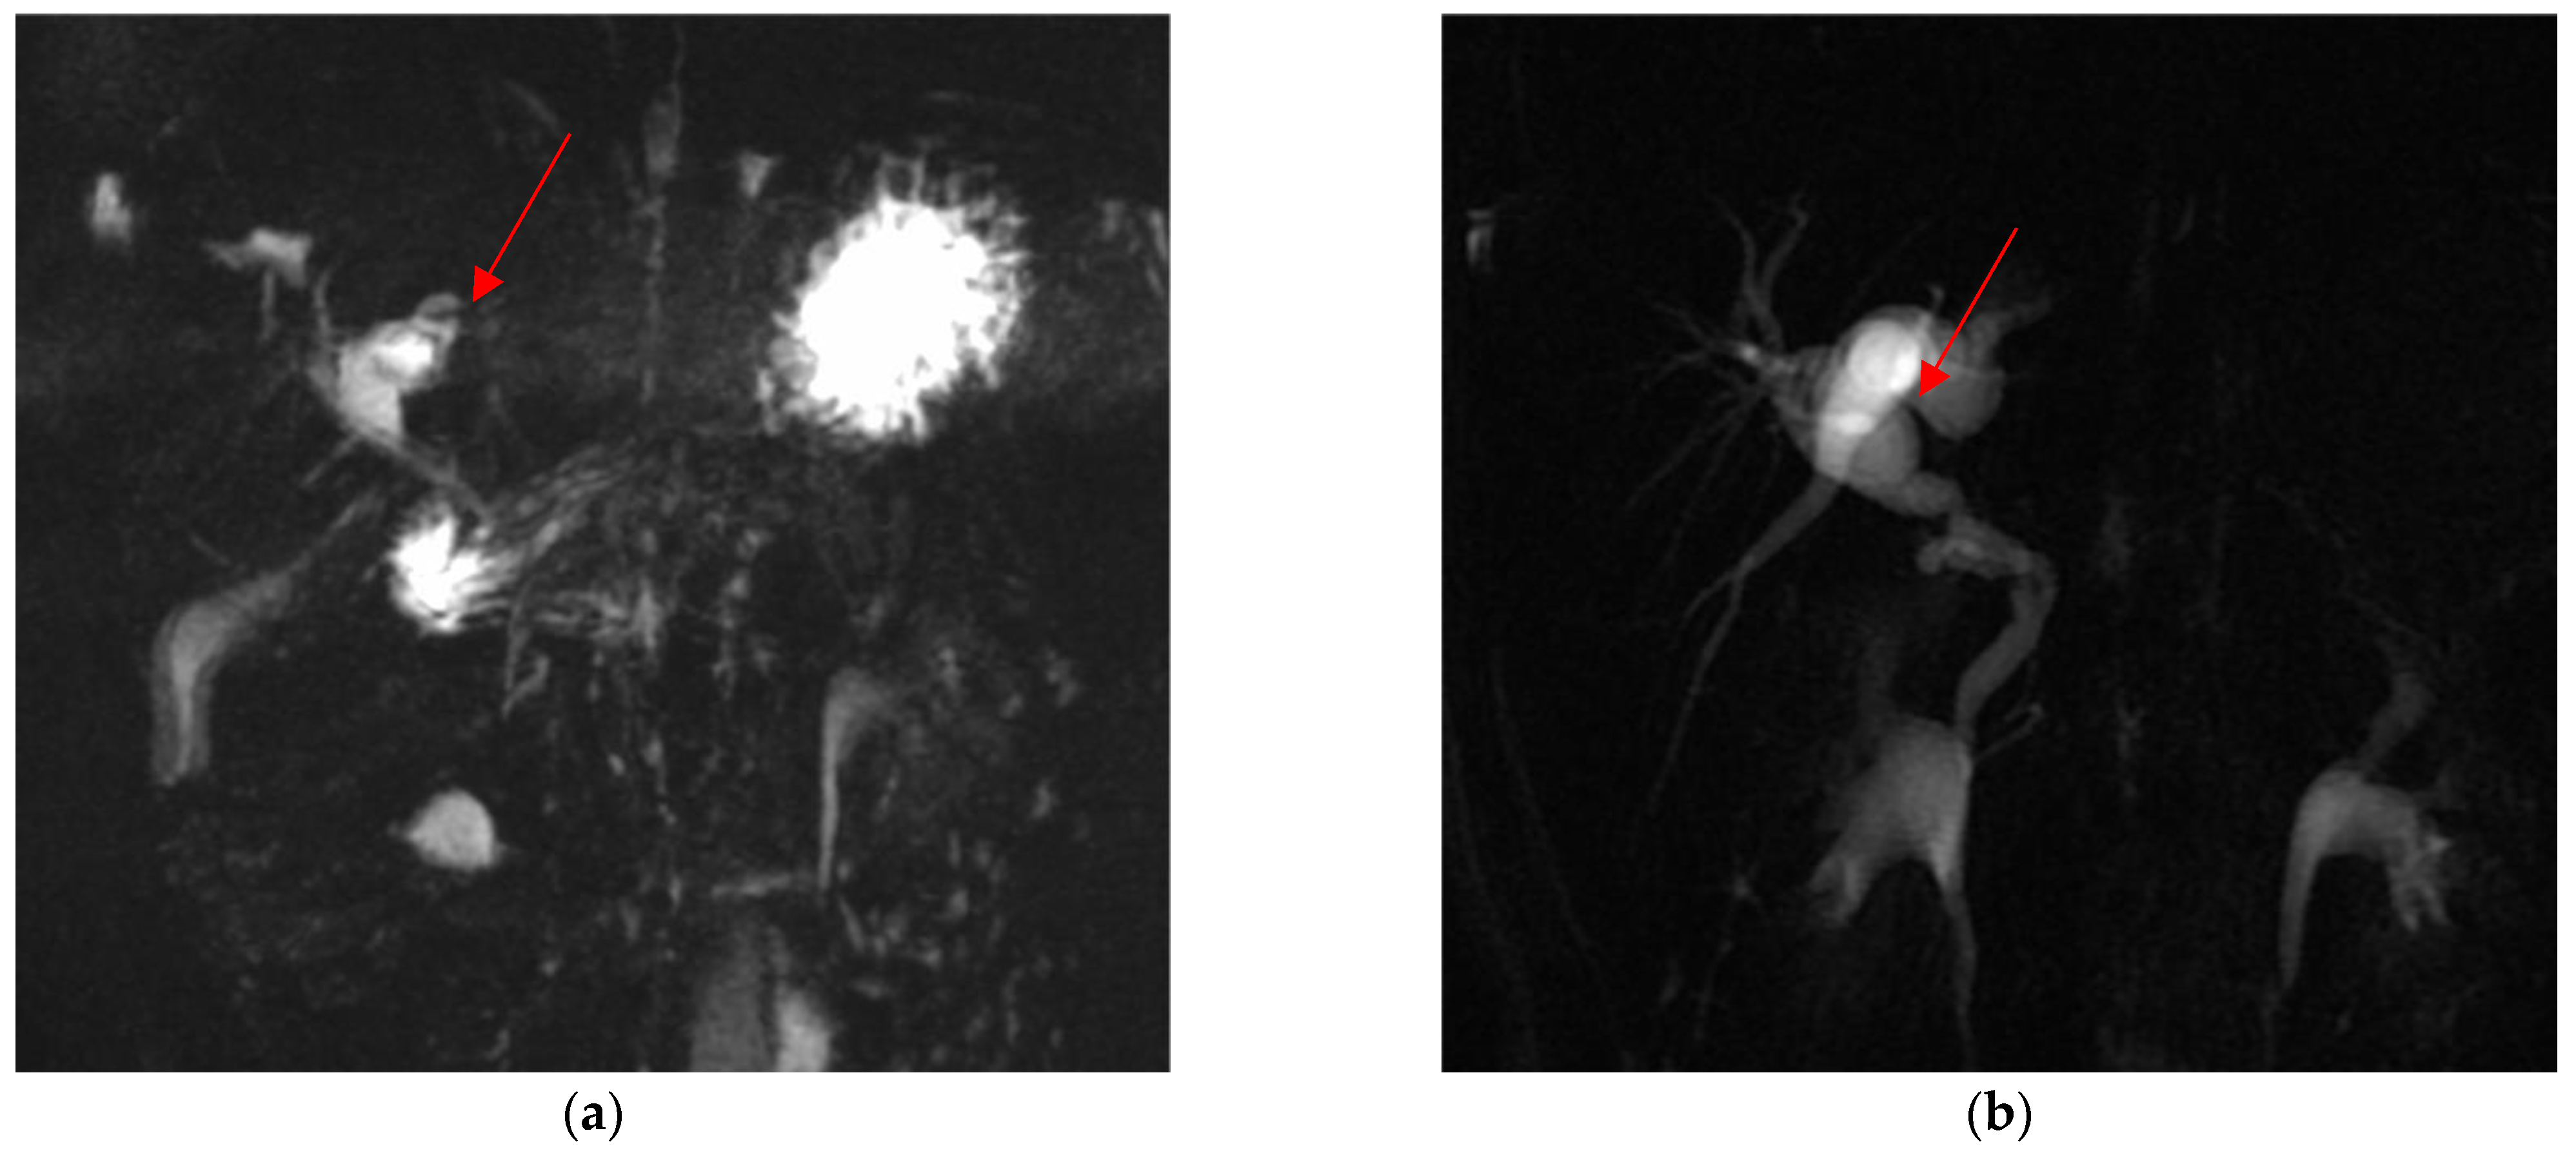

| Cholangio-MRI | Dysmorphic inflamed gallbladder with tiny infundibulum and convoluted cystic duct | Presence of gallstones | Anomaly in the biliary tract anatomy: cystic duct projected into an aberrant right anterior hepatic duct | Presence of gallstones | Presence of gallstones |